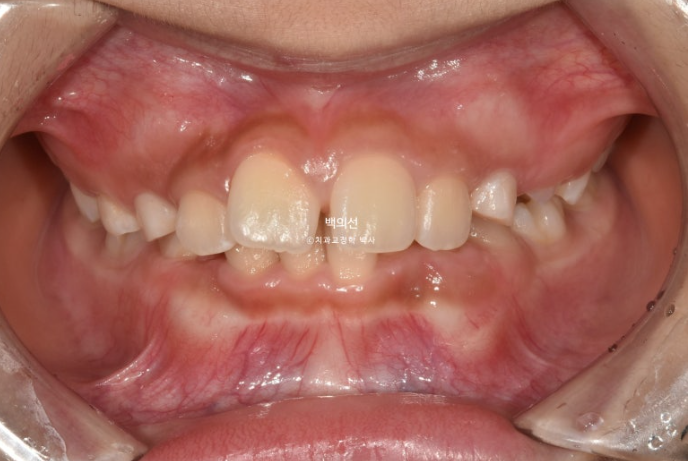

교정치료를 위해 온 만 9세 어린이입니다.

부모님이 고치고 싶은 것은 앞니가 깊게 물리는 과개교합

아래 앞니가 보이지 않을 정도의 심한 과개교합입니다.

앞니 돌출이 있으며

악궁전반부가 좁습니다.

아래도 마찬가지로 악궁확장이 필요합니다.

이 날 공간이 부족하여 앞니가 삐뚤게 나왔고 곧 나올 송곳니는 공간이 부족하여 덧니로 나올 상황입니다.